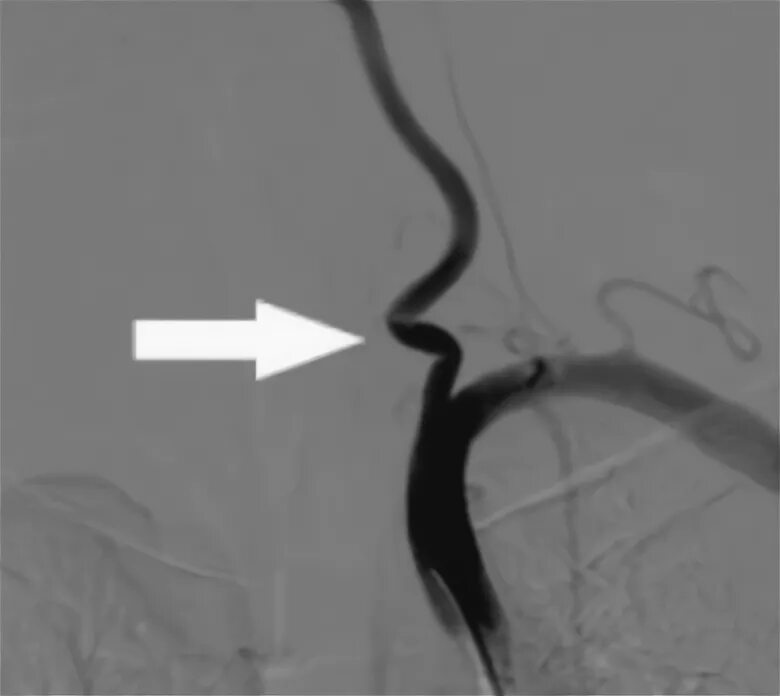

С образная извитость артерий